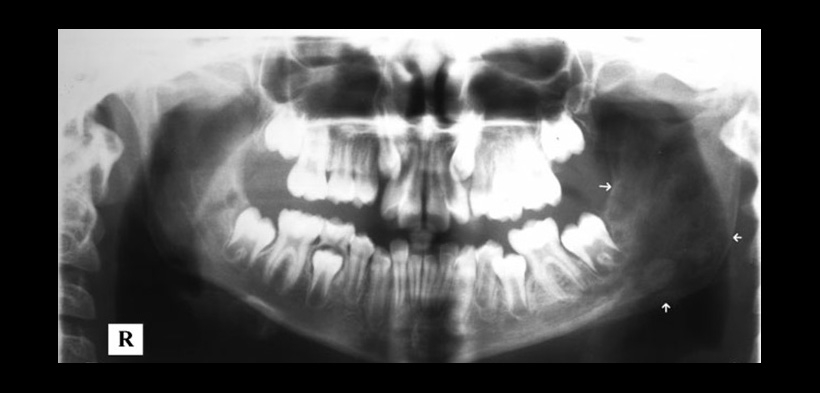

Como se ya se mencionó la OMRC es poco común en los maxilares y en las radiografías panorámicas (fig.1) se puede confundir con otras patologías como la displasia fibrosa, osteomielitis esclerosante o periostitis osificante difusas crónicas. Las radiografías pueden mostrar osteolisis en las primeras etapas, pero luego se podrá evidenciar lesiones hiperostósicas y escleróticas pueden ser vistos en las etapas posteriores, las reacciones del periostio pueden ocurrir en cualquier etapa.

Fig. 1. Radiografía panorámica que demuestra la expansión de la rama izquierda (flechas) y un patrón trabecular alterado.